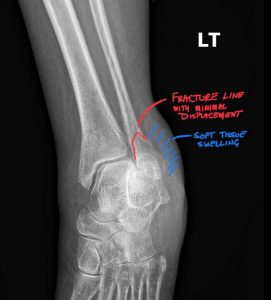

Fig. 3 Annotated xray demonstrating fracture line with minimal displacement and soft tissue swelling

The Fracture Line: Is it visible? Where is it located relative to the joint line (Weber classification A, B, or C)? What is its orientation (transverse, oblique, spiral)? Are the fracture edges sharp (indicating an acute injury) or sclerotic (suggesting an older, non-united fracture)?

Displacement: Are the fracture fragments still aligned, or have they shifted apart? Displacement of more than 2 mm is generally considered significant.